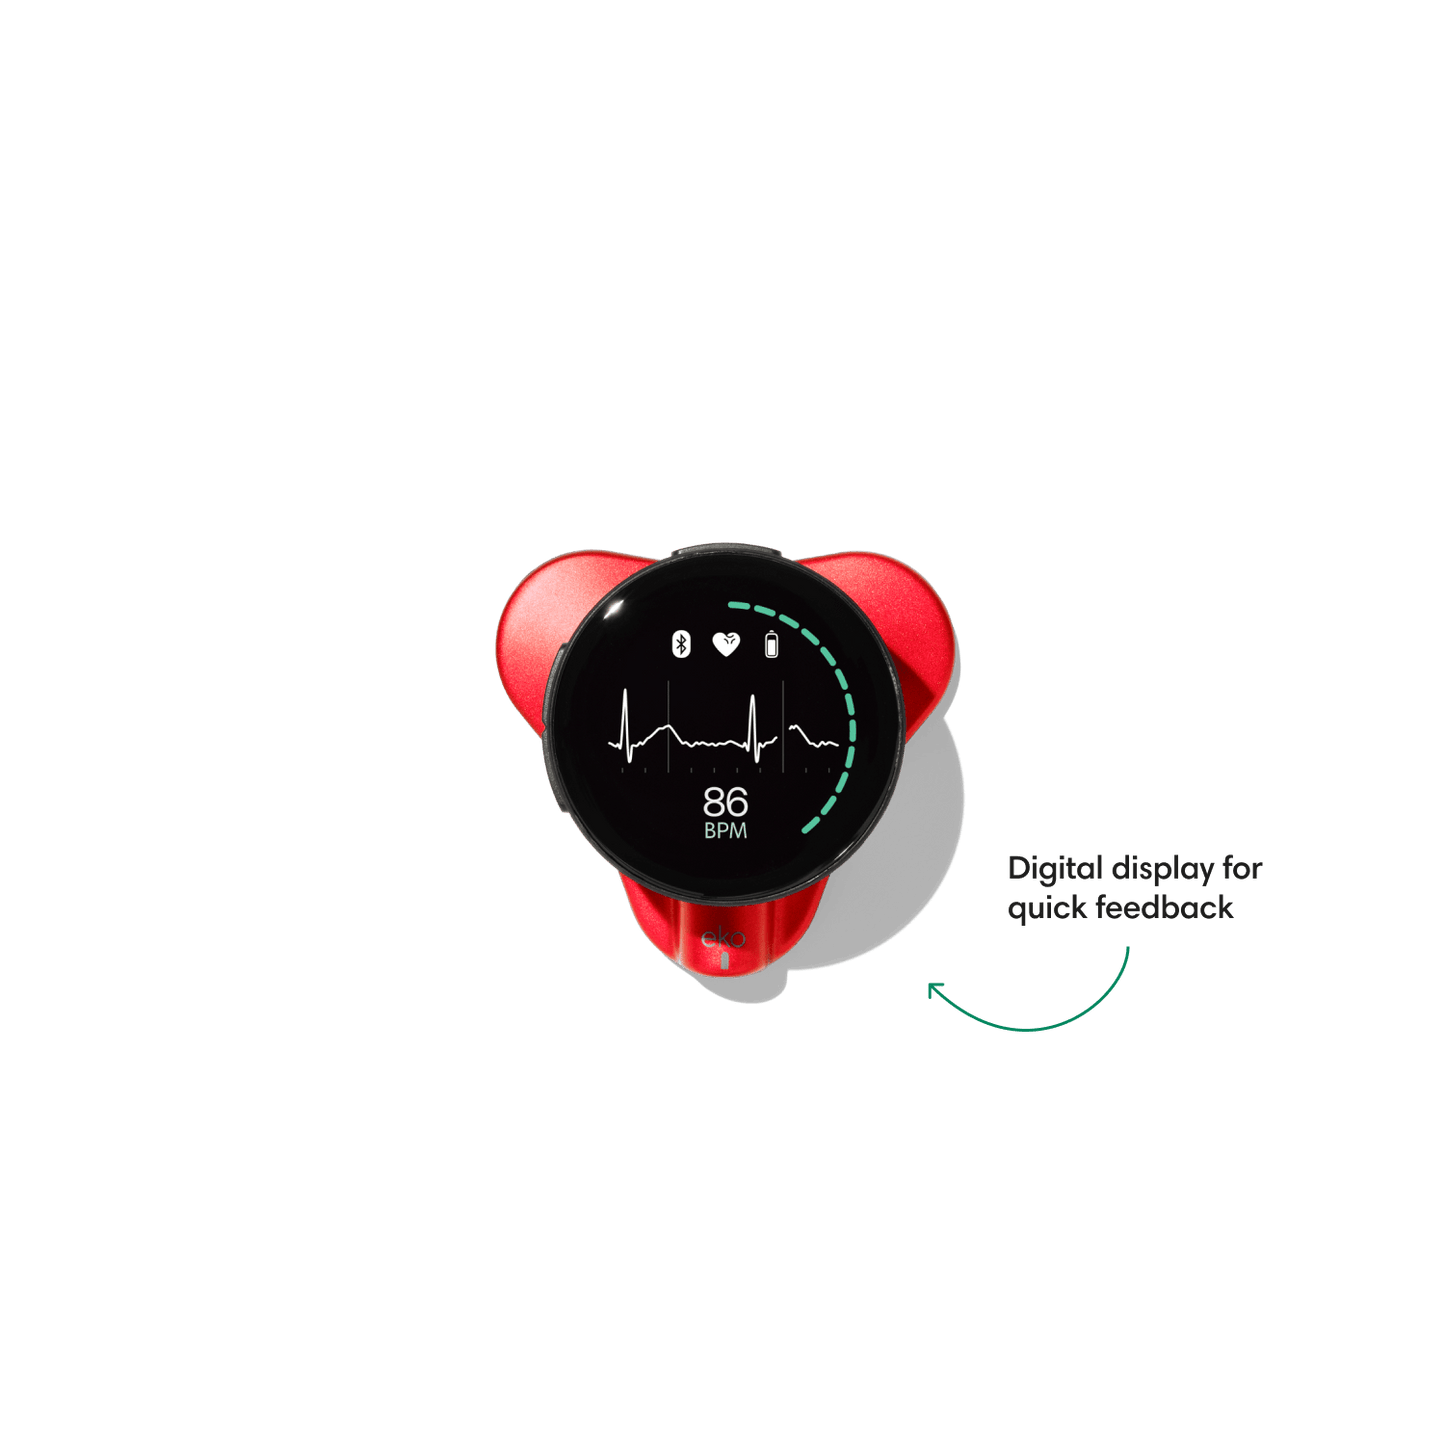

Go beyond sound alone.

For the first time ever, measure heart rate, visualize 3-lead ECG, and see detection results — right on a built-in, full-color display.